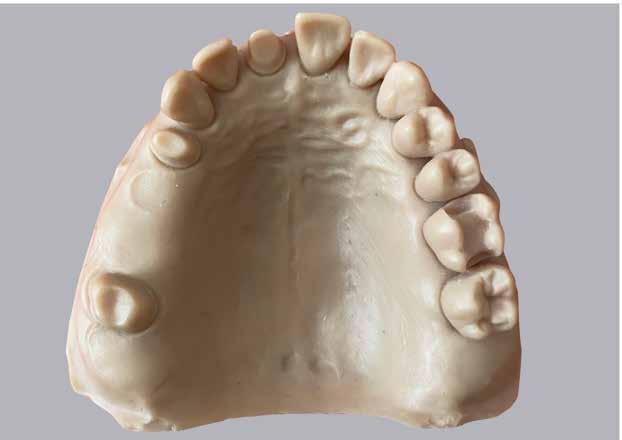

A gyakorlatban a digitális tervezést, illetve az előállítást (marás vagy 3D nyomtatás) megelőzi a lenyomatvétel, amely történhet digitális úton intraorális szkennerek alkalmazásával [11, 12] (1. ábra).

folytonosság megszakadás azt jelenti, hogy egy adott intraorális szkenner a digitális lenyomatvétel során hányszor veszíti el a képet. A vizsgálat ezen részéhez egy polimetilmetakrilát (PMMA) referenciamintát szkennelünk (3. ábra), illetve a pontosság vizsgálatához is ezeket az STL fájlokat használjuk fel. A PMMA modellről egy ipari szkenner (stereoSCAN neo; AICON 3D Systems GmbH, Braunschweig, Németország) segítségével referencia adathalmazt hozunk létre és ehhez hasonlítjuk a vizsgálat során létrehozott fájlokat. A pontosság mérése munkacsoportunk által előzetesen leírt protokoll szerint zajlott [20]. A klinikai szkennelések során a szkennelési idő kerül feljegyzésre teljes állcsont és kvadráns digitális lenyomatvétel esetében. Eredményeinket kiegészítjük szubjektív véleményünkkel, amelyet egy 10 kérdésből álló kérdőív kitöltésével mérünk fel. Az ár–érték arány ismerete végett – a gyártási éveket figyelembe véve – a szkennerek árát is megjelenítjük a weblapon. Fontos kiemelni, hogy a készülékek klinikánkra történő kiszállítási napján a hazai forgalmazóktól oktatást kaphattunk a szkenner használatáról és a szoftverek funkcióiról. Az oktatást eltérő módon oldották meg a forgalmazók: legtöbb esetben a hazai forgalmazó cég képviselői tartották, de